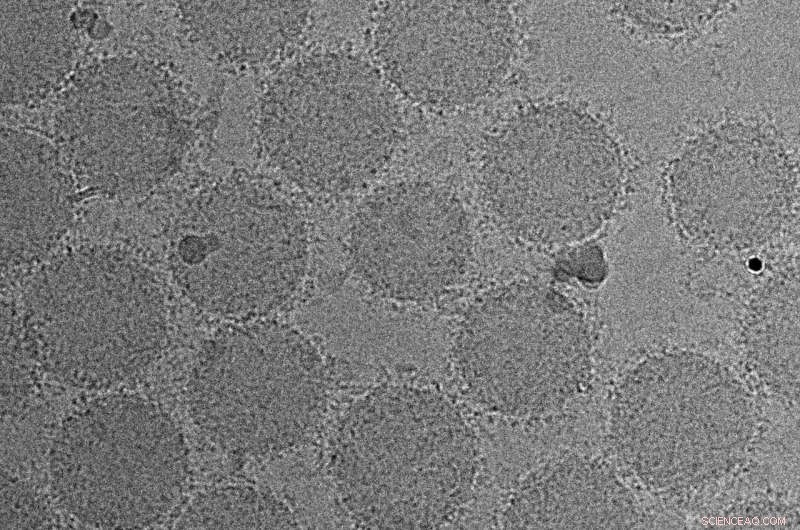

Transmission electron microscopy image showing the formation of biomolecular corona around the surface of nanoparticles. Credit: Morteza Mahmoudi, Brigham and Women's Hospital

Through previous investigations, Morteza Mahmoudi, Ph.D., now a biomedical investigator in the Department of Anesthesiology, Perioperative and Pain Medicine, and colleagues have shown that biomolecules in the blood of healthy individuals and patients form various corona profiles around nanoparticles. Like dipping a donut hole in powdered sugar, nanoparticles collect a unique coating of proteins from the blood. In a new study published in the Royal Society of Chemistry's peer-reviewed journal Nanoscale Horizons, Mahmoudi and the team present evidence that these coronas are personalized and precise, with different compositions or patterns in people with cancers. They have developed a sensor array that has been tested on blood samples, both from people diagnosed with five different types of cancer as well as purportedly healthy people who went on to have a cancer diagnosis several years later. The team's goal is to develop an early detection test that could be used in the clinic to identify those at risk of cancer and other diseases.

To carry out their investigation, the team combined the concepts of disease-specific protein coronas with sensor array technology. Sensor arrays can identify a wide variety of interacting chemical and biological compounds all at once rather than in isolation. To test blood samples for early patterns of disease, the team developed a sensor array that consisted of three different cross-reactive liposomes—fatty molecules that caused protein coronas to form around them. The team tested samples from five patients, each with a different form of cancer: lung cancer, glioblastoma, meningioma, myeloma, and pancreatic cancer. The team found that the selected pattern of corona composition, through advanced classification techniques detected by the nanoparticle sensor array, provided a unique "fingerprint" for each type of cancer. The team also tested the tool using blood from 15 people who were subsequently diagnosed with brain, lung, and pancreatic cancer up to eight years later, finding that their approach could identify and discriminate the cancers at the very early stages.